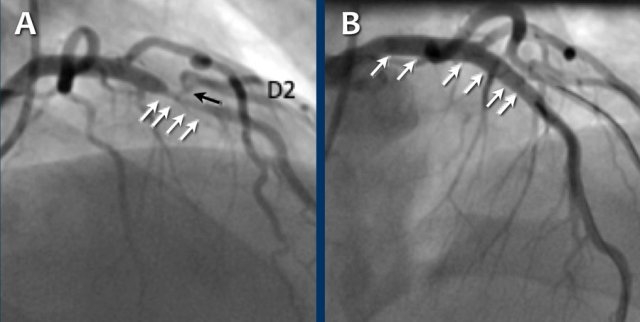

Due to the degree of stenosis and the presence of napkin-ring sign (visible on

axial images) this patient underwent ICA where the presence of severe stenosis

was confirmed.

Continue with the next images...

A: ICA correlates with CTA and shows an 80% stenosis in the mid LAD (white arrows) and a 60% stenosis in the D2 branch (black arrows). The D2 stenosis was overestimated on CTA.

B: PCI was performed during which a drug eluting stent (DES) was implanted with good results (white arrows).